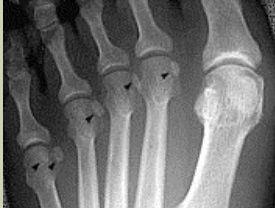

| Describe the alignment of metatarsal 2 | There is no angulation nor displacement of the distal segment relative to the proximal segment. |

| Describe the alignment of metatarsal 3 | The distal segment is displaced laterally (50% apposition) and angulated medially. |

| Describe the alignment of metatarsal 4 | The distal segment is displaced laterally (75% apposition) but there is no apparent angulation. |

| Describe the tubulation of the metatarsals | Metatarsals are overtubulated - decreased girth. |

| Describe the tubulation of the metatarsals | Metatarsals are undertubulated - increased girth. |